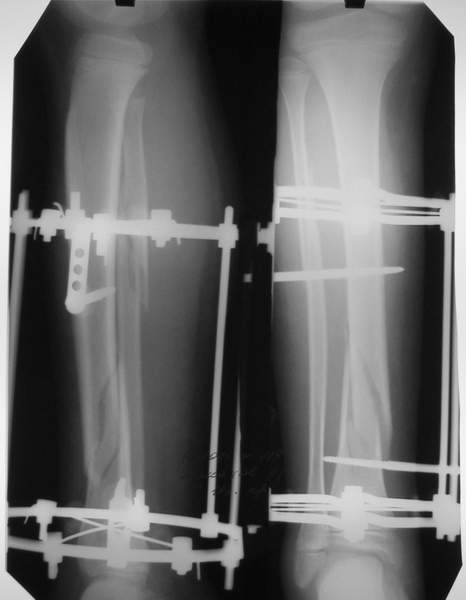

Под рукой прилагаемый пример. Как видите, "стриптиз-аппарат" (шутка проф. З.К.Башурова): 3 кольца-2 кольца-2 полукольца. В случае, который представил Евгений, характер повреждения позволил бы сразу использовать аппарат на основе 2 колец; в крайнем случае прокс. опора м.б. демонтирована сразу после репозиции.

В аттачтах №№ 1 и 2 - примеры, когда 2 кольца не позволили послеоперационно

исправить смещение фрагментов большеберцовой (по ширине и вальгусное).

А казалось бы (#2) - поиграй на штангах и все влетит.

Оперировал не я

В аттачте № 3 - один из примеров полукольцевого аппарат...

Это уже я баловался.

Итог? Работы больше (по времени и

интраоп "подгонке"), срастается также, а особого преимущества по сравнению с

"чиста" кольцевым (вес, удобство ношения и пр.) - я, по крайней мере,

не нашел.

Теперь не балуюсь.